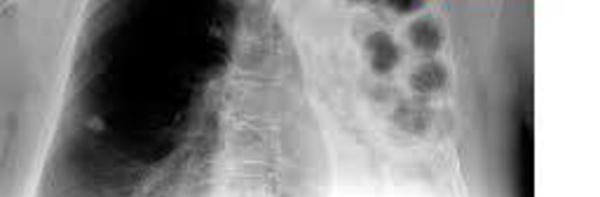

Le Sénégal à l’instar de la Communauté Internationale célèbre la journée mondiale de lutte contre la Tuberculose ce Mardi 24 mars 2014 à Kaffrine. Le thème retenu est: « Atteindre les manquants ». L’objectif est de contribuer à l’atteinte l’objectif global des trois millions au niveau mondial. Neuf (9) millions de personnes par...